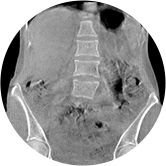

• 全身姿态评估

WR-3D能提供一种负重位状态下全身的姿态和三维空间任一平面平衡评估,使全脊柱术后评价更客观、真实 。通过各种临床参数包括骨盆、脊柱参数评价骨盆、脊柱平衡,避免由于髋膝屈曲造成的代偿性脊柱失衡的发生,WR-3D提供了三维空间任一平面平衡评估测量方法,可以更加定量地评估手术效果 。